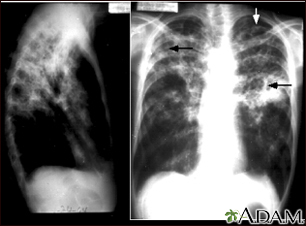

Tuberculosis avanzada, radiografía de tórax

La tuberculosis es una enfermedad infecciosa que causa inflamaciones, formación de tubérculos y la aparición de otras expansiones tisulares que pueden causar necrosis tisular. Estas radiografías de tórax muestran una tuberculosis pulmonar avanzada en la cual se observan varias áreas claras (opacidades) de diferentes tamaños, unidas unas con las otras (coalescencia). Las flechas señalan la localización de las cavidades de estas áreas claras. La radiografía de la izquierda muestra claramente que las opacidades están localizadas en el área superior de los pulmones, vistas desde la parte posterior. Esta es la apariencia típica de la tuberculosis pulmonar crónica, pero también puede ocurrir en la histiocitosis pulmonar crónica y en la coccidioidomicosis pulmonar crónica. La tuberculosis pulmonar está reapareciendo nuevamente con una mayor resistencia que la hace difícil de tratar; la tuberculosis pulmonar es la forma más común de la enfermedad, aunque otros órganos también pueden ser infectados.